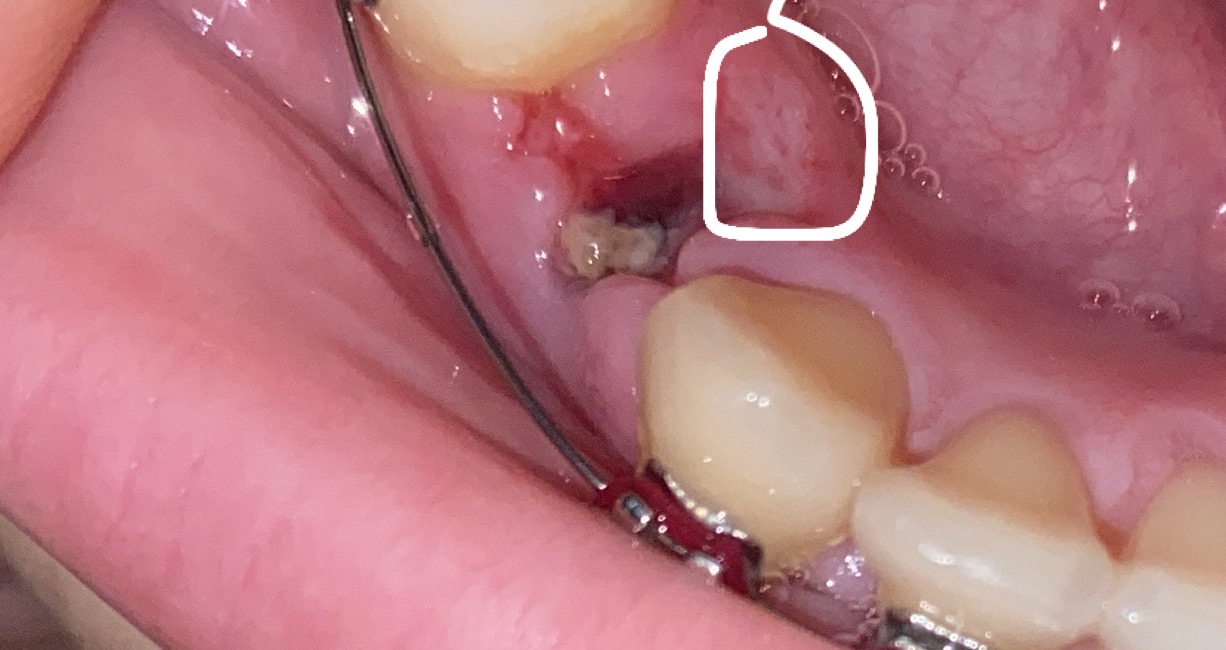

ถอนฟันมาวันที่18ก.คนี้ก็ครบ1อาทิตย์แล้วค่ะแต่ว่าตรงแผลถอนฟันไม่ปวดแต่เจ็บตรงที่วงกลมไว้แบบบนี้อักเสบไหมคะหรือเป็นร้อนใน